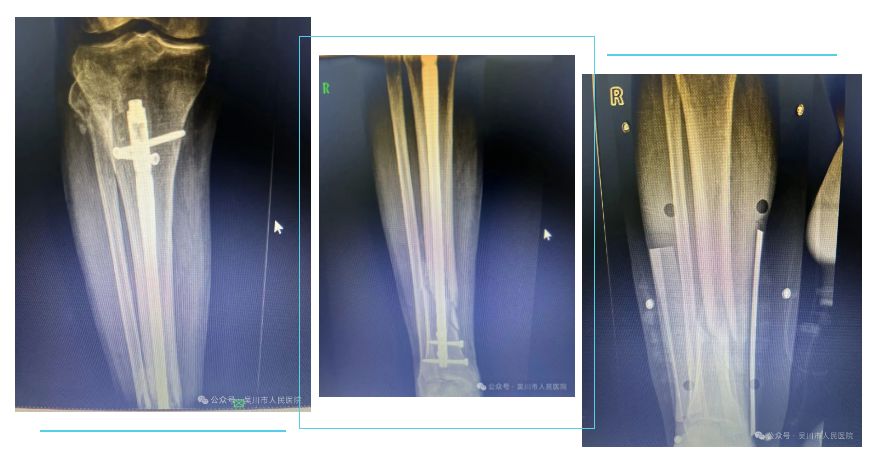

病例三:该患者为96岁老年患者,诊断:右胫骨下段开放性骨折,入院后给予胫前皮肤清创缝合术+托具外固定术,胫前皮肤愈合后给予髓内钉复位内固定术,术后顺利康复出院。